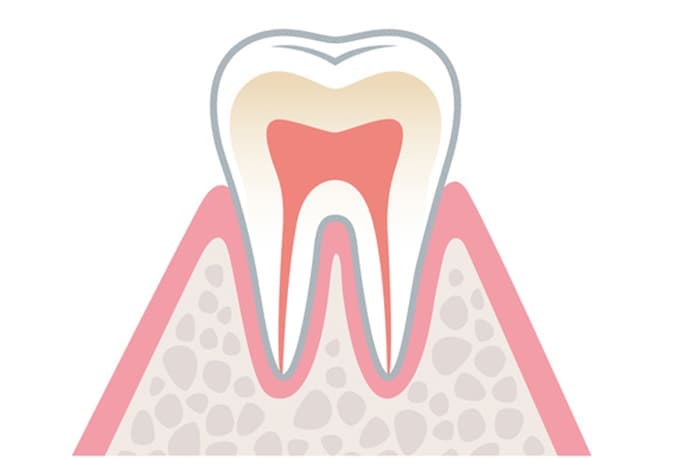

歯周病を予防するには?

歯周病は正しいブラッシングと生活習慣、定期健診を受けることで予防できます。